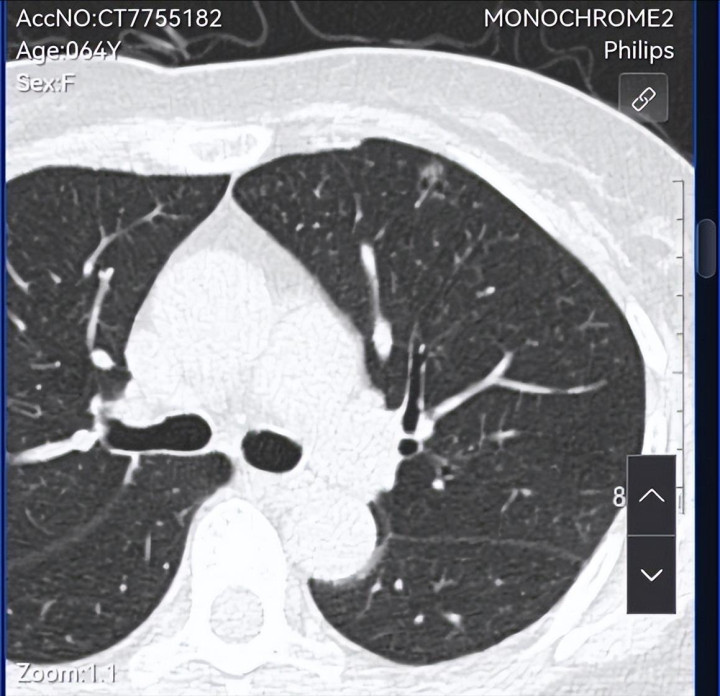

这几年体检发现多发结节,本年的是不是有变化了,是否需要手术,请咱们信任的戴主任会诊,是否不错传云影像可能看的更显着。九故十亲齐来这里请咱们信任的戴主任调理,期待着主任的会诊。